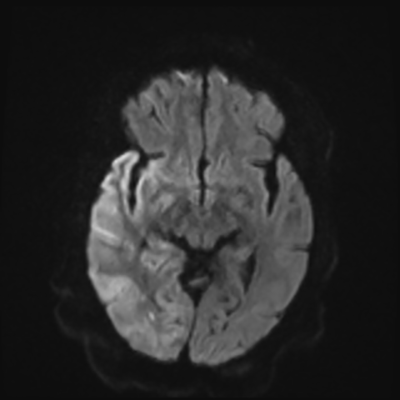

You come back the next day and see how things are going. The patient's electrographic record has shown a moderate encephalopathy (diffuse slowing, disorganization) with frequent right posterior quadrant delta slowing. Based on this result, and an adequately improved clinical examination, you give the okay to proceed with obtaining an MRI of his brain. This is shown below.

MRI brain (DWI)